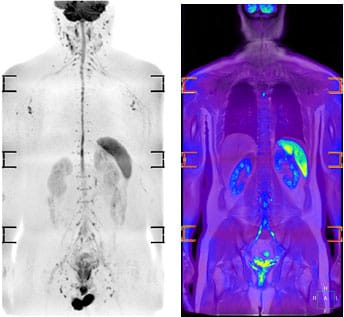

BodyDWI 体幹部拡散強調画像について

2018年4月より、BodyDWI体幹部拡散強調画像(いわゆるDWIBSドゥイブスDiffusion-weighted Whole body Imaging with Background Suppression)を撮影することができるようになりました。

この検査は体幹部のがんの病巣発見や転移巣の検索、化学療法や放射線治療によるがんの治療効果判定などに用いることができ、簡易的にPET検査のような画像を撮像できることから非常に注目されている検査の一つです。特徴として、放射線被ばくがないので繰り返し検査ができ、造影剤や放射性医薬品の注射をする必要がありません。検査時間は30分程度で、検査費用はPET検査の6分の1程度で負担が少ない検査です。

他のMRI検査と同様に、MRI非対応の金属(心臓ペースメーカーなど)がある患者さまは検査できません。